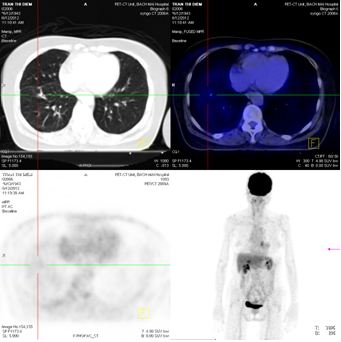

CT lồng ngực (12/12/011)

Hình 3: Hình ảnh chụp CT lồng ngực - u thùy dưới phổi phải: 28× 25mm, kèm theo nốt mờ nhỏ xung quanh

Chụp PET/CT toàn thân sau 6 tháng điều trị:

Trước điều trị : Khối u thùy dưới phổi phải 2,6 × 2,8 cm, Max SUV = 5,32

Sau điều trị 6 tháng: U tan gần hoàn toàn

Hình 7: Hình ảnh PET/CT toàn thân sau 6 tháng điều trị: Khối u phổi tan hoàn toàn